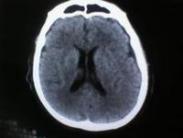

腔隙性腦梗死(lacunar infarction)是一集病理-CT-臨床為一體的概念。是老年人的常見病,高發年齡組在60~70歲。Fisher將其概述為:發生于腦深穿通動脈(或其他微小動脈)的缺血性微梗死(或軟化灶),經慢性愈合后所形成的不規則腔隙。病變累及的微小動脈直徑在200μm左右,病理改變為2~20mm的腔隙或梗死灶,頭顱CT掃描顯現為2~20mm(一般不應超過15mm)的不同程度的密度減低區,目前臨床已可診斷20多種腔隙綜合征。